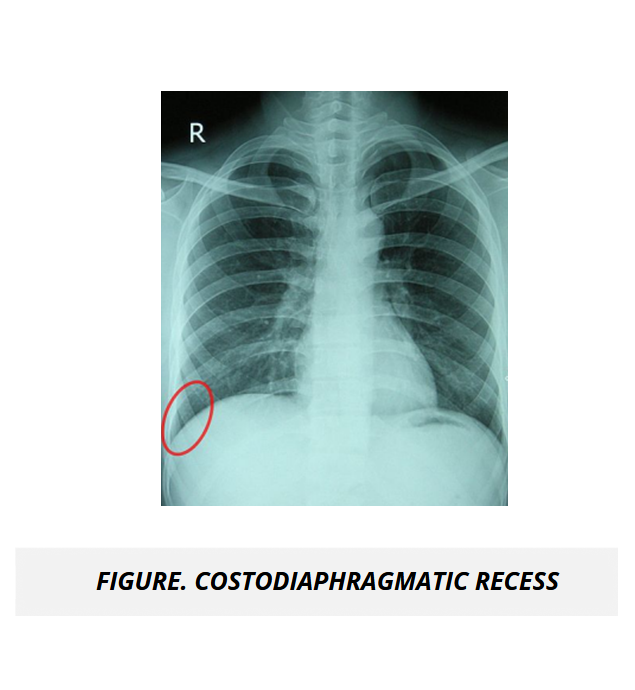

The UMock USMLE® Step 1 prep course features high quality pathologic images, gross and microscopic views, as well as radiologic imaging illustrating key concepts, disorders, and abnormal processes to help you gain a complete understanding of subject material.

The course includes high quality radiological images and microscopic views highlighting normal and abnormal processes specific to renal and urinary diseases to give you a distinguished understanding of the application of concepts in clinical scenarios.